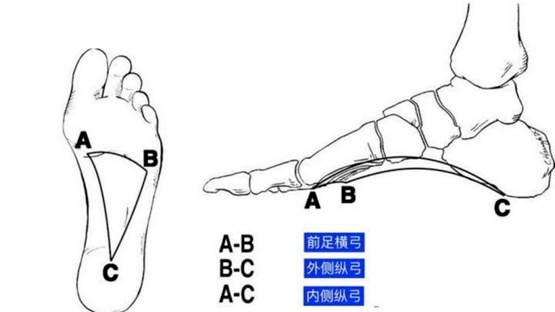

人到18岁左右,一切的足部骨骼、韧带才干发育彻底,构成老练的足弓结构,足弓是由跗骨、跖骨的拱形砌合,以及足底的韧带、肌腱等具有弹性和缩短力的安排一起构成的一个凸向上方的弓。

正常发育彻底的内侧纵弓曲度大、弹性强,就像一个小型减震器。咱们每走一步、跳一下,它都能缓冲来自全身骨骼和关节的压力,让脚部能给身体供给满足的安稳支撑,咱们才干跑跑跳跳无压力。

那么,具有“踩屎感”的鞋对咱们的足弓有什么害处?

“踩屎感”凉鞋由于鞋底平、软、宽,中部承托力不行,无法支撑咱们的足部和下肢,也就无法让脚找准走路的着力点。